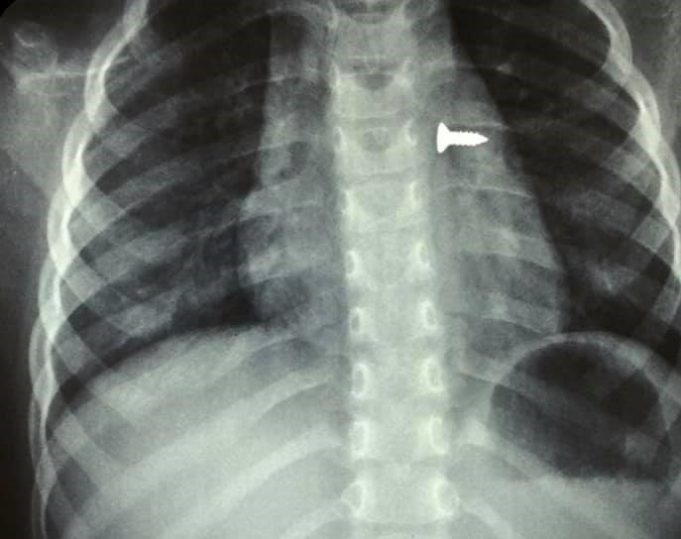

Αφαίρεσαν βίδα από τον αριστερό πνεύμονα τρίχρονης (εικόνες)

Με επιτυχία ολοκληρώθηκε η επέμβαση στο ΠΑΓΝΗ για την αφαίρεση βίδας από τον αριστερό του πνεύμονα τρίχρονου κοριτσιού!

Σύμφωνα με τον αναπληρωτή καθηγητή ΩΡΛ της Ιατρικής Σχολής Κρήτης, Μανώλης Προκοπάκης, σε ανάρτησή του στο Facebook το περιστατικό έγινε χθες και η εικόνα από την ακτινογραφία του μικρού παιδιού είναι συγκλονιστική.

Ο ίδιος αναφέρει στην ανάρτησή του «πολύ επείγον χειρουργείο! Πριν από λίγο. Αφαίρεση βίδας από αριστερό βρογχικό δέντρο τρίχρονου κοριτσιού. Πολύ επικίνδυνο…».

Το παιδί παραμένει για νοσηλεία στην Παιδιατρική Κλινική του ΠΑΓΝΗ.